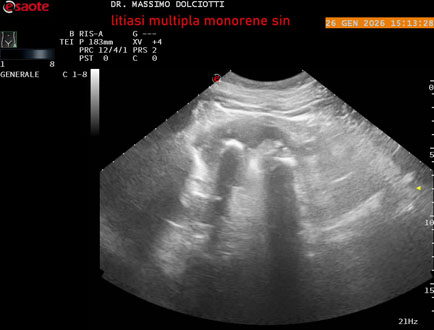

Data inserimento: 29/01/2026

Ecografia del: 26/01/2025

Strumento: Esaote MyLab Eight

Sonda: Conevx Multifrequenza 1-8 MHz

Età Paziente: M 78 anni

Motivazione dell'esame: follow up di litiasi al rene sinistro, in paziente sottoposto a nefrectomia destra.

Commento all'esame: le immagini ed il video documentano il rene sinistro in sede, di ecostruttura disomogenea per evidenza di multiple formazioni litiasiche al pielone superiore, delle dimensioni di 15,9 mm, al pielone medio di 17,5 mm e al pielone inferiore di 18,9 mm e morfovolumetria normale, con diametro bipolare di 115 (v.n. 90-120 mm) x 54 mm e parenchima renale dello spessore di 17 mm ( v.n. > 13 mm).

Conclusioni: litiasi multipla del monorene sinistro (multiple lithiasis of the left solitary kidney).

In collaborazione: Dr.ssa Marica Manfredi - Ancona, Dr. Ilir Qose - Ancona

Presentazione: Dr. Massimo Dolciotti - Ancona

Elaborazione digitale: Andrea Dini - Ancona